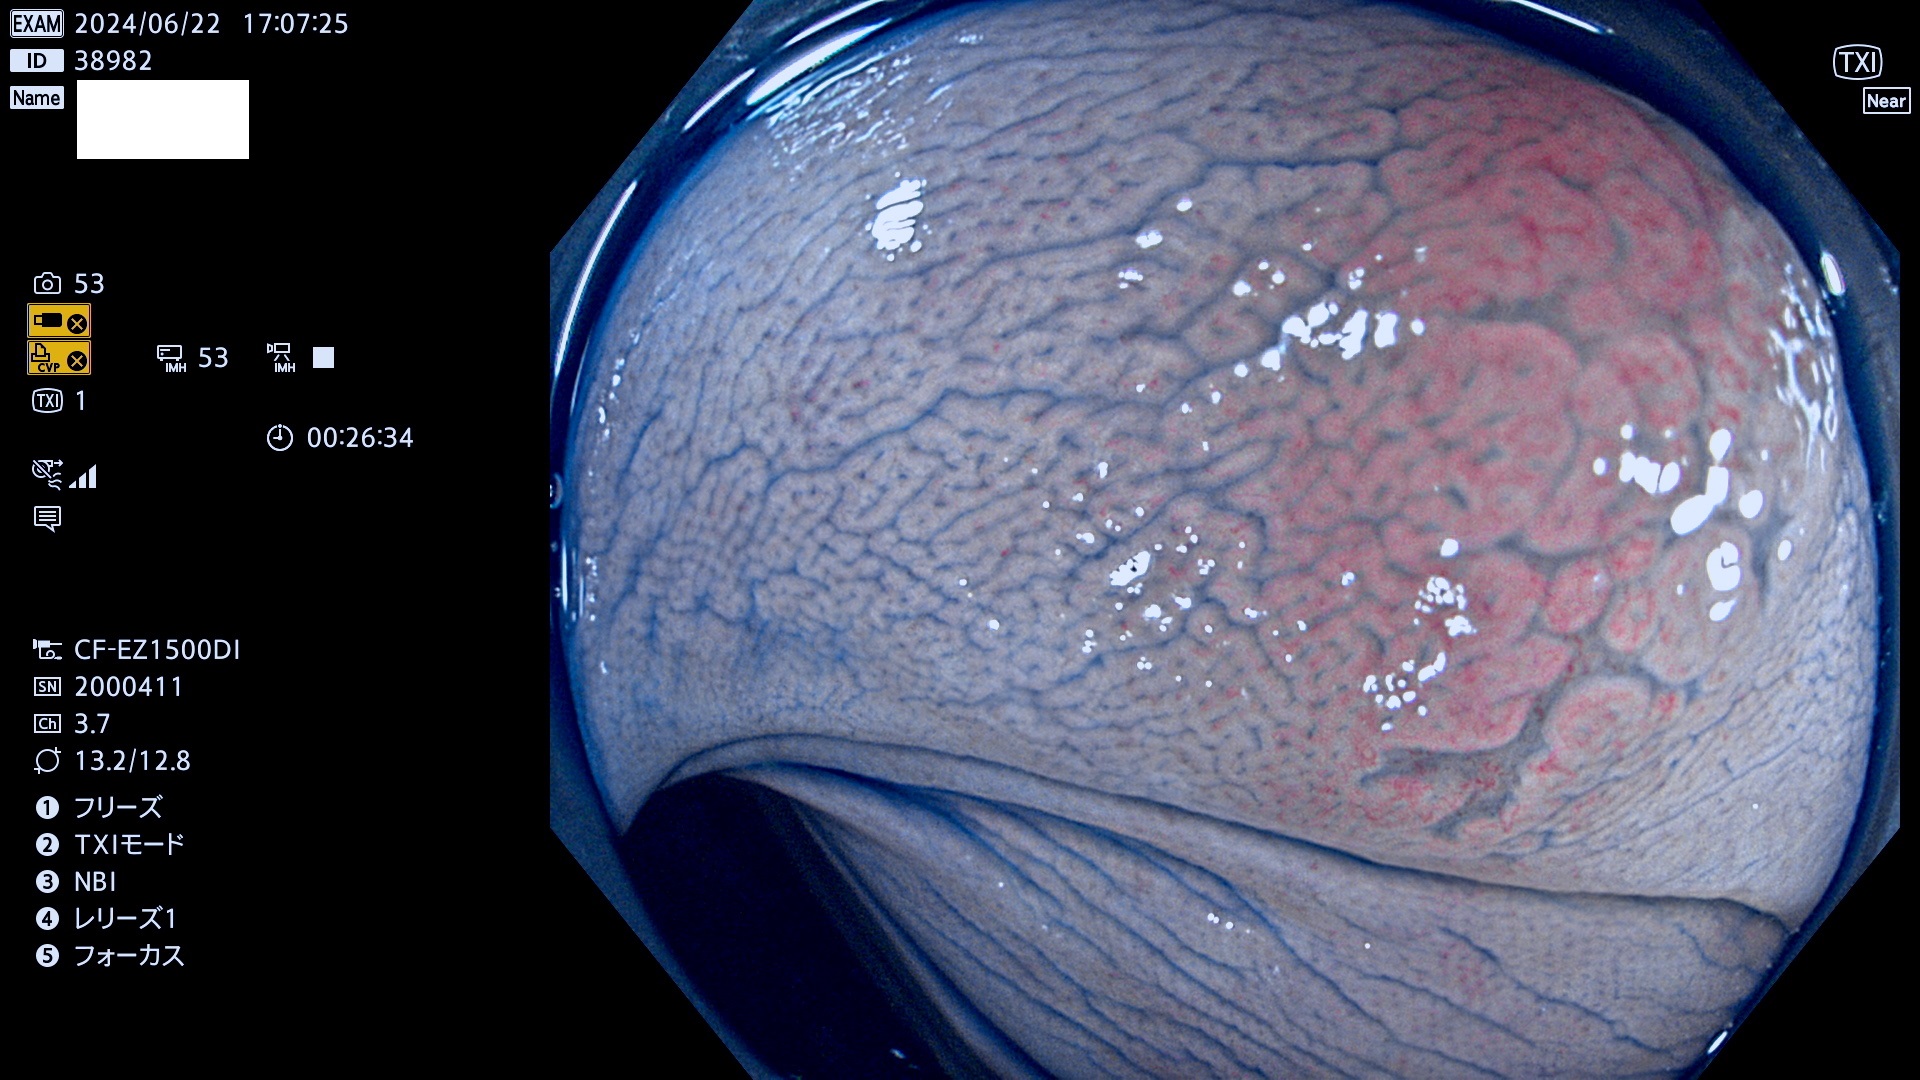

今週のUb、Uc型腺腫

完全に平坦な物をUb、陥凹している物をUcと呼びます。最も発見が難しく危険な病変です。

抽出の対象期間 2024年6月20日〜6月24の5日間(40件の検査)6件 (6/40=15%)